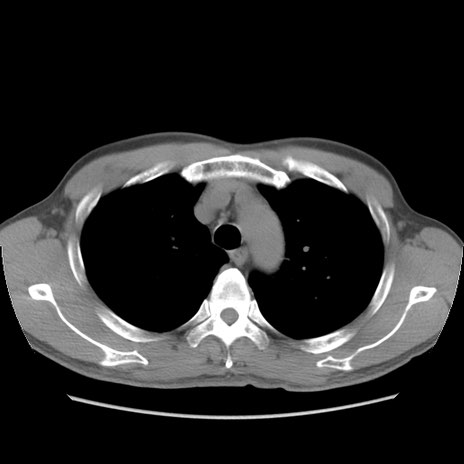

症例56 CT(横断像)

脂肪ウインドウ